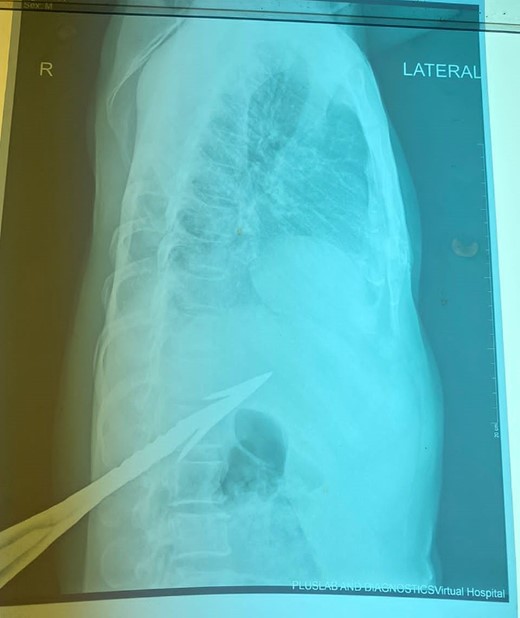

HB 9.9 mg/ml, sodium 135 mmol/L, chlorine 103 mmol/L, potassium 3.8 mmol/L, urea 4.3 mmol/L, and creatinine 108.5 umol/L. During the erect chest X-ray, the medical team observed the head of the spear within the abdominal cavity (Fig. 2), and a lateral chest X-ray confirmed its position in an ascending orientation (Fig. 3). The abdominal ultrasound showed the presence of a foreign body with an acoustic shade inside the liver parenchyma (Fig. 4); no free fluid was found in the Morrison’s pouch, but about 90 ml of free fluid was shown in the Douglass pouch. Both pleural spaces were free of fluid and had no pericardial fluid. We evaluated and discussed the possibility of performing an abdominopelvic computed tomography, but it was not feasible due to the patient's financial constraints.